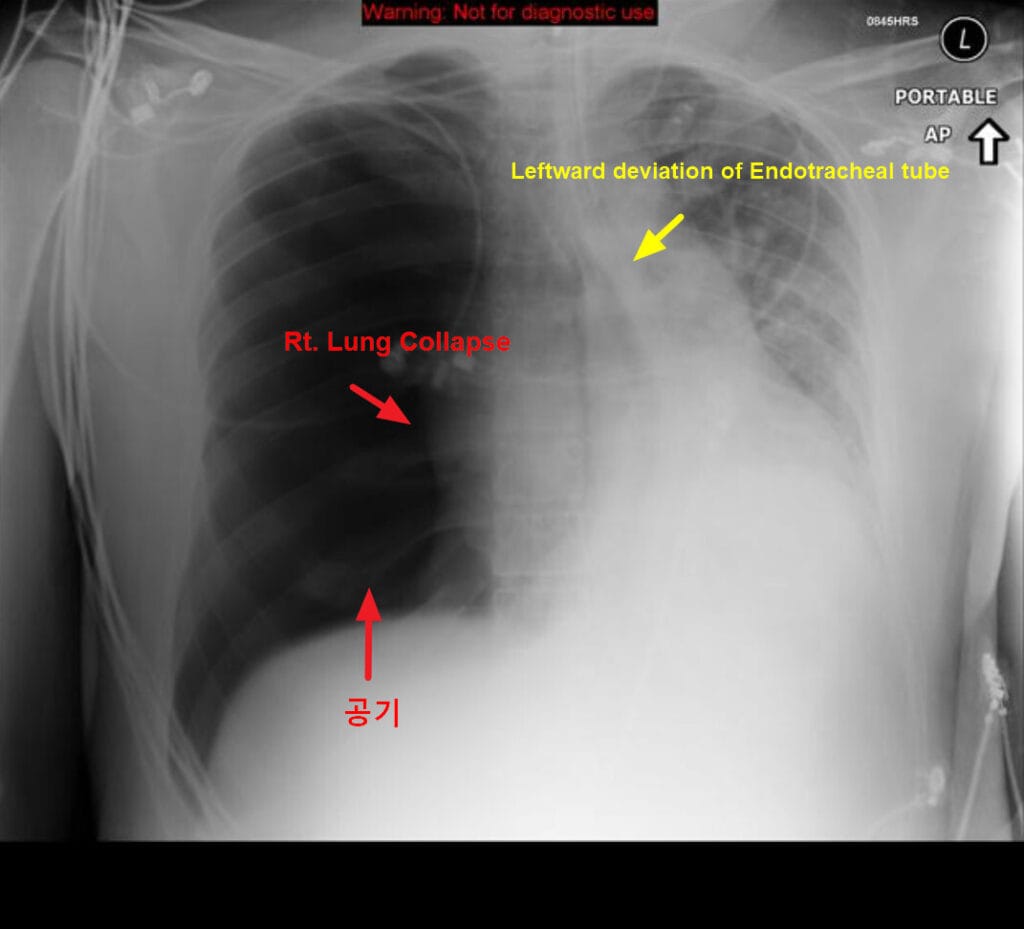

| 🔵 흉부 X선 (Chest X-ray) |

| 긴장성 기흉이 의심되는 경우 치료 후 확인 목적으로 촬영하며, 종격동 편위와 폐 허탈 소견이 나타납니다. |

긴장성 기흉의 종격동 편위와 폐허탈 소견을 간결하게 설명한 그림이 있어 가져와봤습니다 🙂

CT에선 이렇게 보입니다.